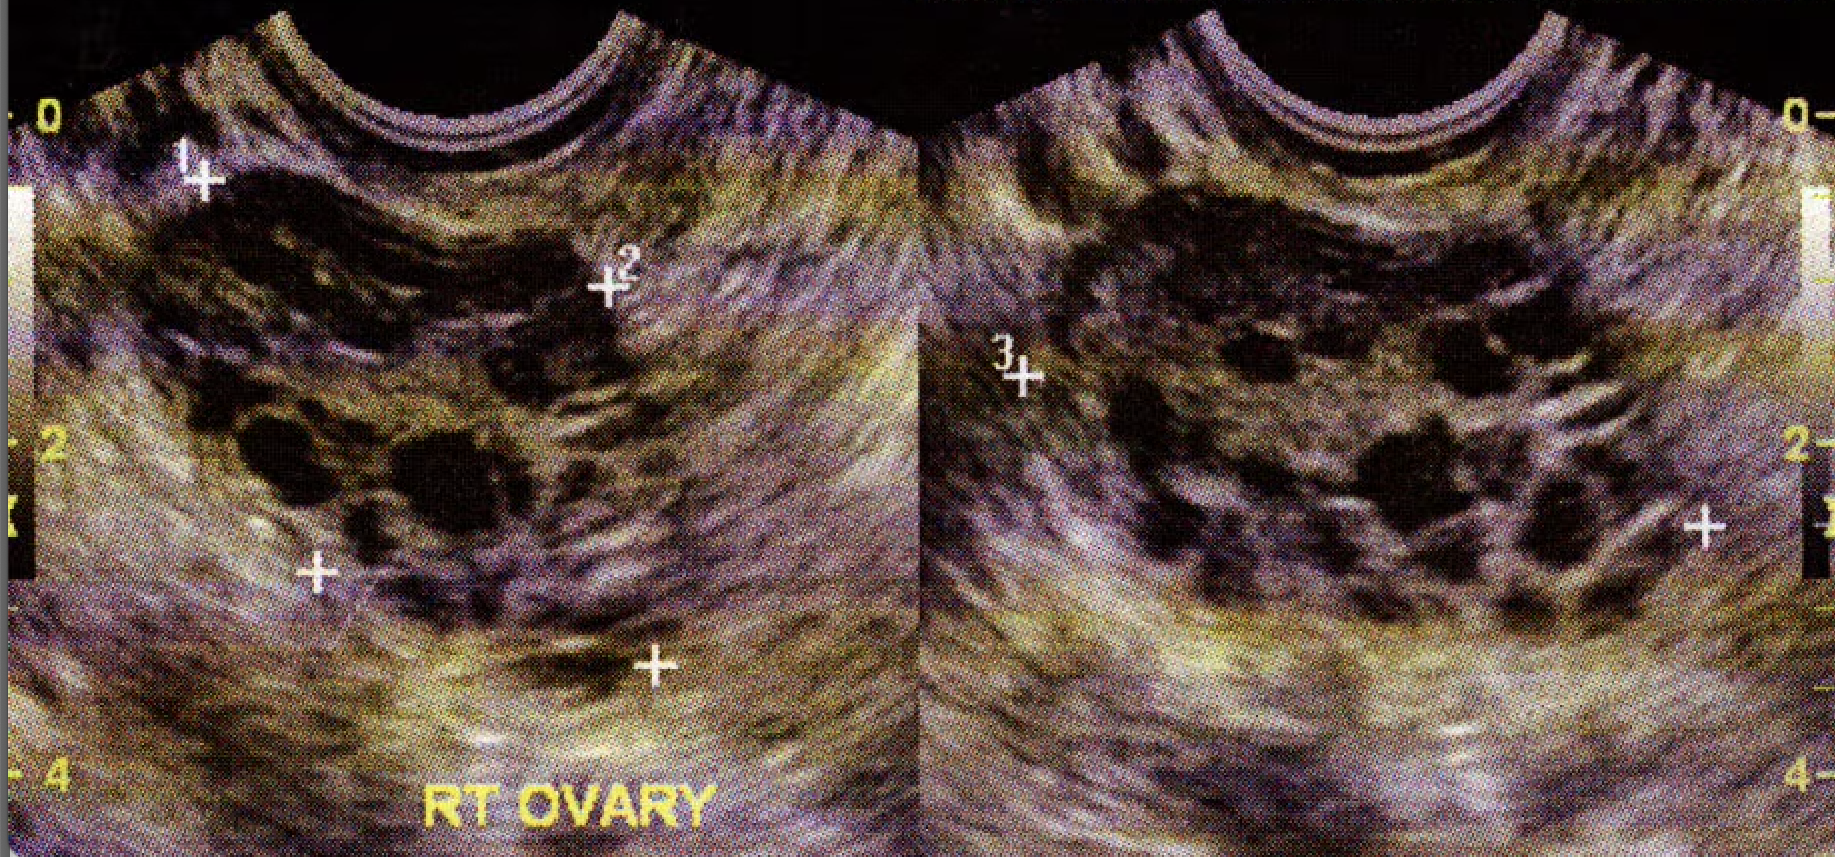

Polycystic Ovaries on Ultrasound